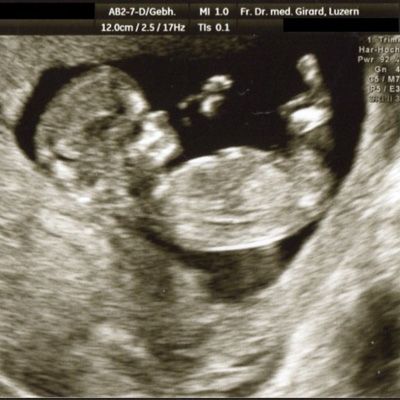

Der Ultraschall hilft uns dabei als einzige Methode, das ungeborene Kind in der Gebärmutter direkt sichtbar zu machen.

können wir die Intaktheit und das Alter der Schwangerschaft feststellen. Diese Information ist von grosser Bedeutung, um beispielsweise in der Spät-Schwangerschaft ein allfälliges vermindertes Wachstum des Kindes erkennen zu können. Auch können Mehrlinge mit hoher Sicherheit erfasst oder ausgeschlossen werden. Zudem kann schon in diesem frühen Alter eine Reihe schwerer Fehlbildungen erkannt werden. Mit der Messung der Nackenhaut-Dicke können Hinweise auf eine mögliche Chromosomen-Störung (beispielsweise das Down-Syndrom = Trisomie 21) erfasst werden.